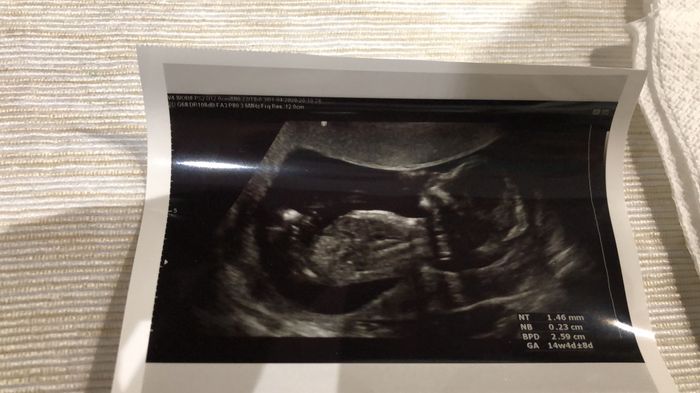

Mancano ancora tantissime settimane alla morfologica, che avrò il 15 Luglio, mi ritrovo spesso a fantasticare se sarà Filippo o Lucrezia, io mi sento maschio ma non si sa mai.

Mi affido a voi esperte di Nub Theory, cosa dite maschio o femmina??